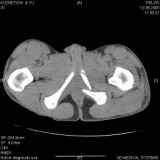

Уважаемые коллеги! Хотелось бы услышать совет по тактике лечения представлленого больного.Поступил после лечения в одном изотделений области. Травма 2,5 месяца назад. После выведенияиз шока был произведен остеосинтез перелома бедра, предплечья, до перевода к нам проводилосьвытяжение по оси шейки бедра за стержень, введенный в большой вертел. На сегодня деформацияригидна, клинически мобильности не определяется. Заранее признателен. P.S. Данный вид травм не включен в перечень "высокотехнологичных операций", направить длялечения по квотам Минздрава очень сложно.

Это обзорные и косые снимки

С уважением,

Leonid